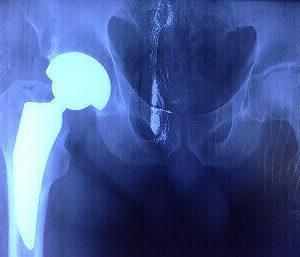

Эндопротезирование

Эта операция способна вернуть полную подвижность тазобедренного сустава. Вместо поврежденного устанавливается искусственный сустав. В полости фиксируют циркониевый или титановый штырь, и туда же вставляют искусственную головку. Ложе синтетического сустава крепят к другой кости.

Головка может свободно вращаться во впадине, при этом больной не испытывает боли и дискомфорта и может жить полноценной жизнью.